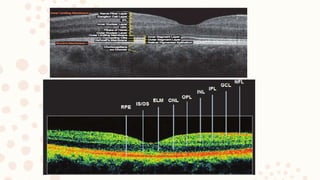

10. OPTICAL COHERENCE TOMOGRAPHY

– It is non invasive noncontact imaging that produce high resolution cross

sectional image.

– Useful in diagnosing macular disorders and to delineate retinal layers and

detect subtle anatomical changes